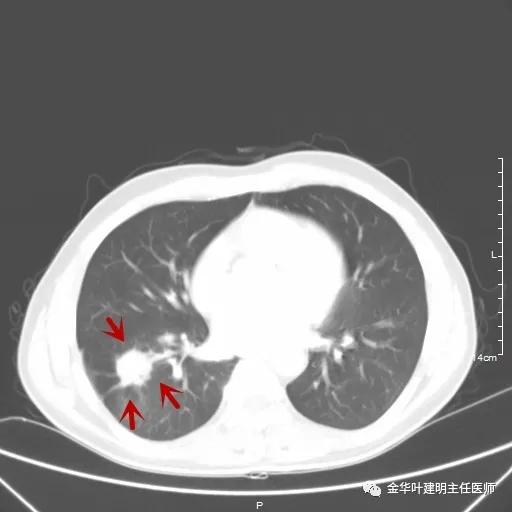

如果选取肿瘤所在的层面来看,则是以下图像:

以上是肺窗,见右肺下叶实性占位,有毛刺、浅分叶、膨胀性,血管征等,是较为典型的恶性肿瘤。